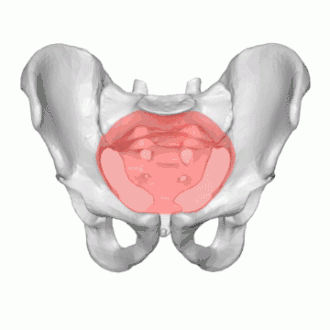

The pelvic inlet or superior aperture of the pelvis is a planar surface which defines the boundary between the pelvic cavity and the abdominal cavity (or, according to some authors, between two parts of the pelvic cavity, called lesser pelvis and greater pelvis). It is a major target of measurements of pelvimetry.

Its position and orientation relative to the skeleton of the pelvis is anatomically defined by its edge, the pelvic brim. The pelvic brim is an approximately apple-shaped line passing through the prominence of the sacrum, the arcuate and pectineal lines, and the upper margin of the pubic symphysis.

Boundaries

The edge of the pelvic inlet (pelvic brim) is formed as follows:

| Anteriorly by the pubic crest (or pubic symphysis) |

| Laterally by the iliopectineal line |

| Posteriorly by the anterior margin of the base of the sacrum (or the ala of sacrum) and sacrovertebral angle (or sacral promontory) |